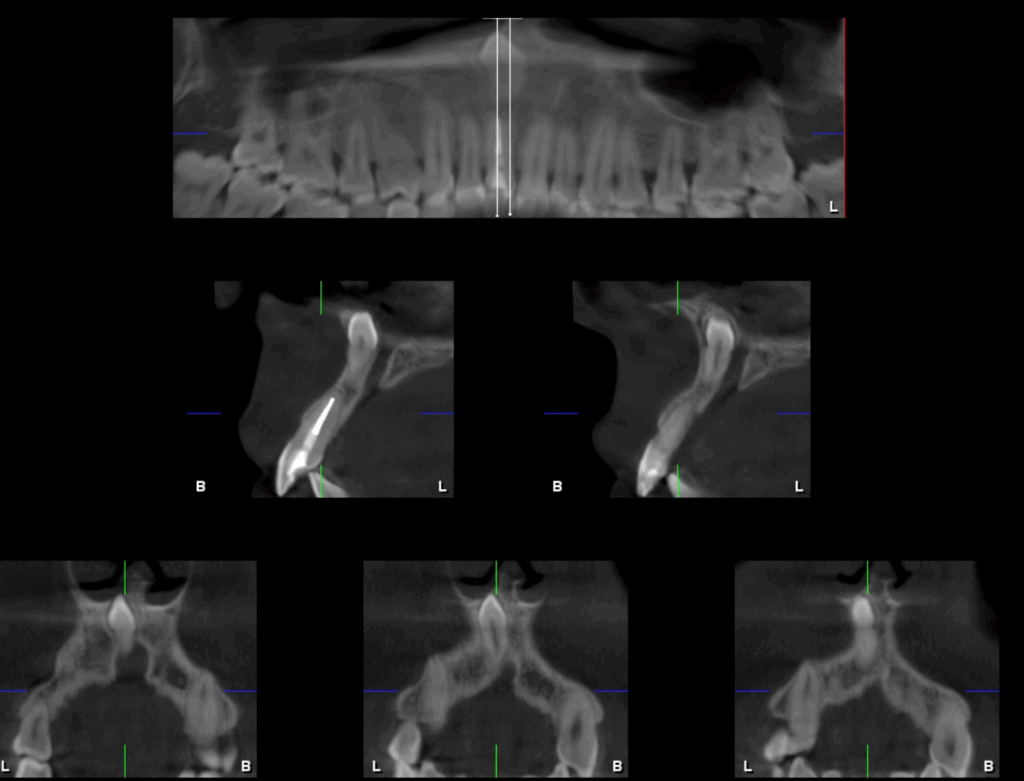

A la evaluación de la tomografía volumétrica (CBCT) en los cortes axiales (Figura 2) y transaxiales (Figura 3), se aprecia pieza supernumeraria en posición invertida localizada a nivel de pieza 11, segmento radicular en contacto con la cortical de conducto nasopalatino, segmento coronario en contacto con el piso de fosa nasal derecha.

CORTES TRANSAXIALES